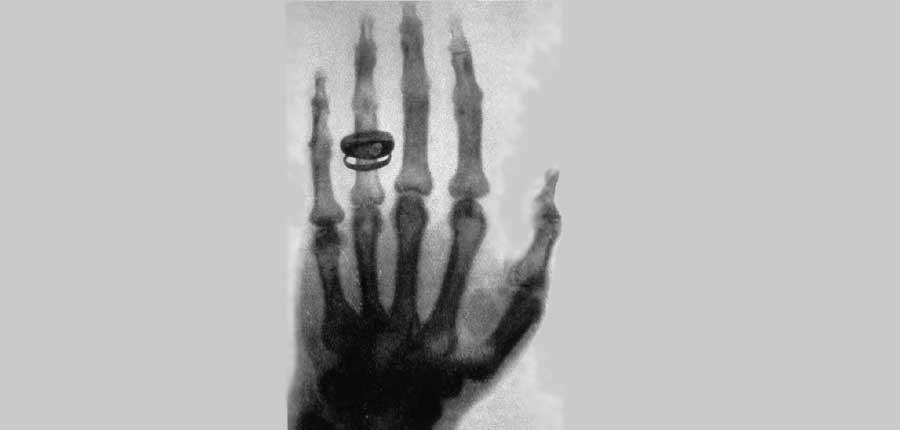

130 Jahre Röntgenstrahlen: Eine Revolution, die bis heute Leben rettet